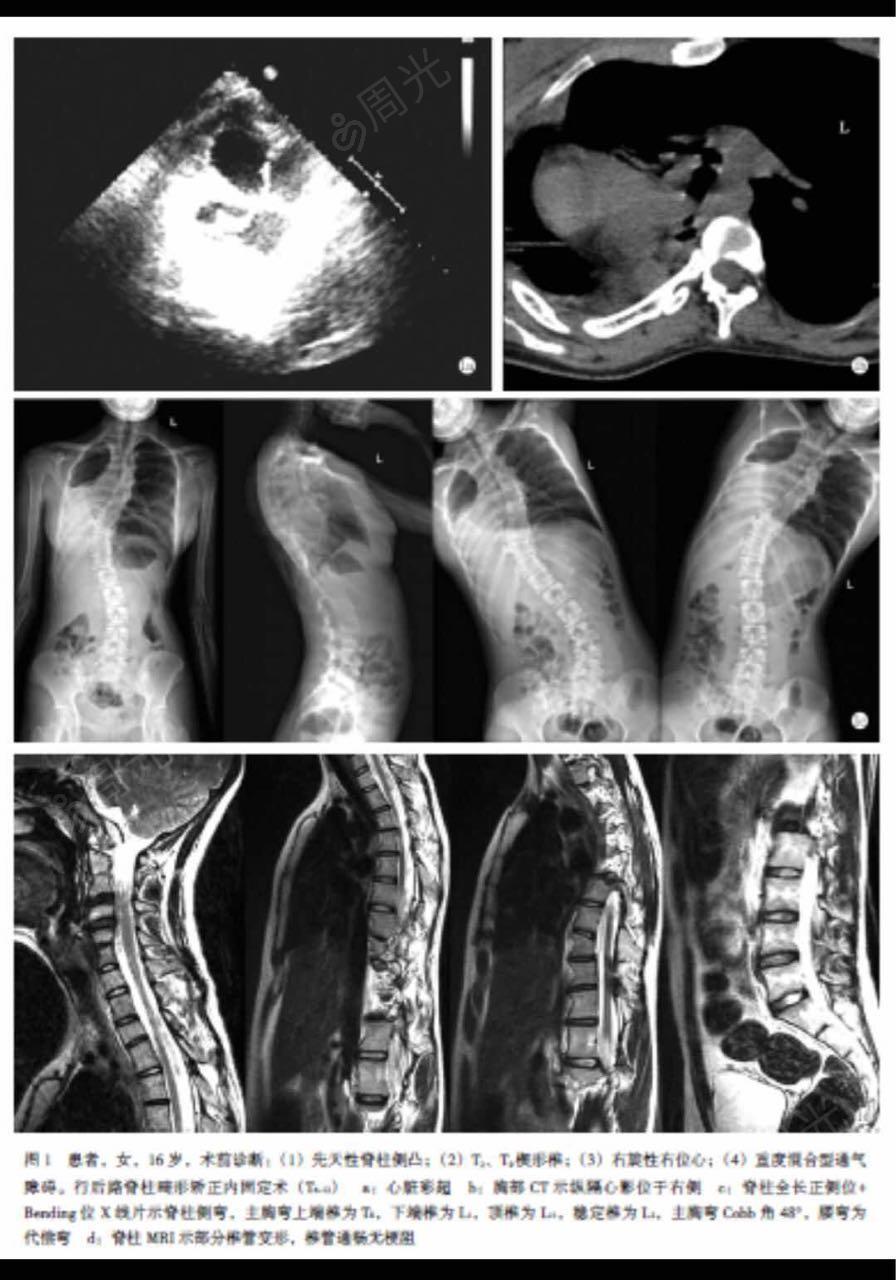

手术经过:患儿全麻下左侧卧于手术台,右肩消毒铺巾,右肩胛后缘中份直

衣领口总歪是脊柱侧弯早期信号##脊柱侧弯康复##微博健康在关注

脊柱呈"s"型侧凸,胸段凸向右侧,左肩稍高,左肩胛骨向后突起,右侧轻度"